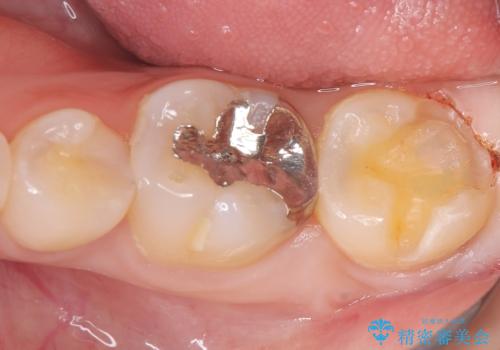

- 初診時にお口の中をチェックしたところ虫歯があり、大きさから部分的な詰め物のお話をしました。材料の特性を説明し、再び虫歯になりにくいセラミックインレーを選択されました。

セラミックインレー接着時にはラバーダム防湿を行いました。